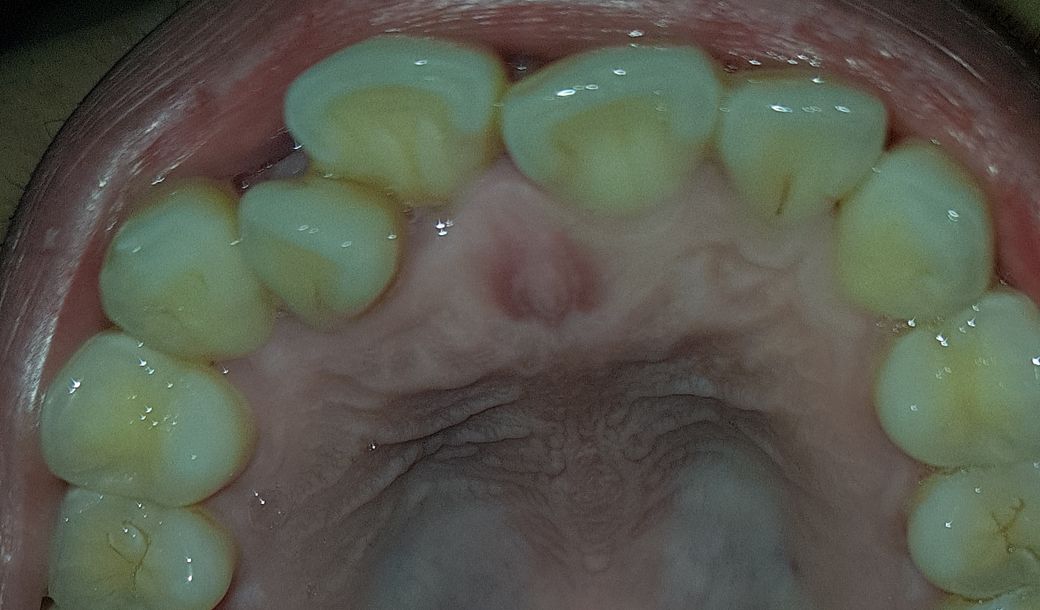

이번주 토요일날 치과가는데 충치인건가요?

충치가 맞는건가요??

1년만에 충치가 진행되기도 합니다..앞니는 치아탈회로 보이며 완성된 형태의 충치가 아니므로 잘 관리하면 충치로 진행을 막을수 있습니다.

현재 사진만으로는 정확한 판단이 어려워 보입니다. 방사선 사진까지의 자료가 필요합니다. 다만 1년이라는 시간이 지나면 충치가 생길 가능성이 충분히 있으므로 갑자기 진행되는 경우도 많습니다.

사진상으로는 크게 충치가 잇어 보이진 않지만, 위 앞이 바깥쪽은 치아가 선천적으로 약하게 태어난거 같으니 관리를 잘해주시는게 좋을것같습니다.